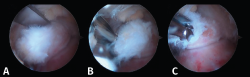

Tras la disección completa del PPA y la evaluación y el tratamiento de la patología asociada del FHL, si es necesario, podemos iniciar el procedimiento de resección ósea(11,12,13). Así, en caso de pinzamiento óseo, los procedimientos se realizan de acuerdo con la etiología de este (Figuras 8 A, B y C).

Figura 8. A: en una primera opción, se realiza la resección ósea mediante un osteotomo de 5 mm; B y C: la segunda opción es realizar la resección mediante el uso de una fresa artroscópica.

Proceso posterolateral del astrágalo hipertrófico o proceso de Stieda

En los casos de PPAH, el hueso se puede cortar mediante el empleo de un osteotomo de 5 mm introducido por el portal artroscópico o resecarse mediante un terminal motorizado de fresa artroscópica. El uso del osteotomo no es fácil debido a que el ángulo del corte no es perpendicular; por ello, la mayoría de las veces es necesario finalizar la resección ósea mediante la fresa de artroscopia.